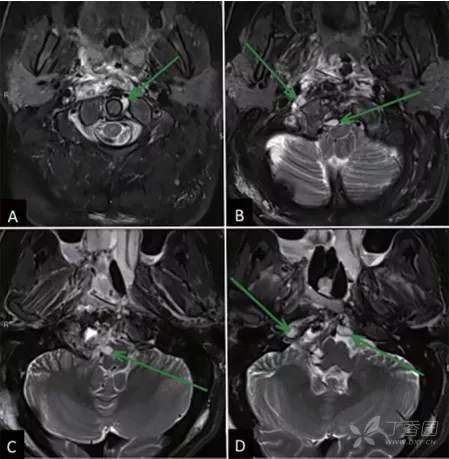

Lariboisiere大学医院的核磁共振成像(MRI)检查显示,肿瘤位于下斜坡,并向周边广泛延伸,右侧C1和C2、岩尖水平均见有肿瘤,右侧椎动脉被肿瘤包绕,脑干受压迫(►图1)。CT扫描也显示骨质广泛的肿瘤浸润。

图1:内镜下鼻内镜入路前的术前影像。

图3,鼻内镜下肿瘤切除术后影像学检查(第一阶段术后)。显示脑干充分减压,正中中线部分肿瘤切除,其他在枢椎齿状突、C1侧方和硬膜内残留肿瘤等待第二阶段开颅手术切除(A-D)(绿色箭头)。

第二阶段:经颅远外侧入路后路固定

肿瘤切除后,进行C0-C1-C2后路固定。两个阶段的病理检查均证实先前诊断脊索瘤,Ki-67指数为10%。术后病程平稳,病情稳定。术后几个月,患者抱怨耳朵疼痛,伴随着中耳积液消退症状好转。术后MRI显示肿瘤次全切除,对侧C1椎弓根仅有少量脊索瘤残留(►图4)。在接下来的几个月内进行辅助质子治疗(总剂量70.2gy),术后随访2年未见肿瘤进展迹象。